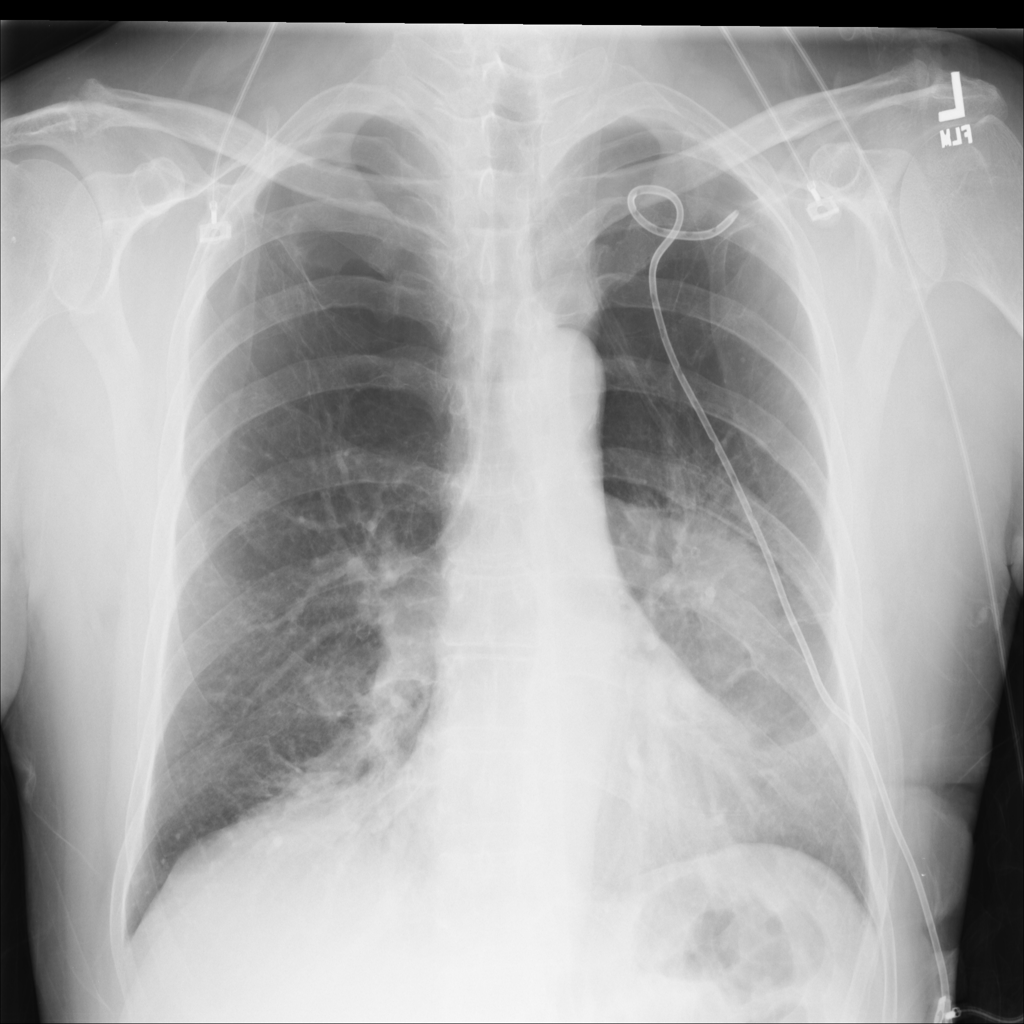

PAT-4639 · IMG-020Pneumothorax

PAT-4639 · IMG-020

PA